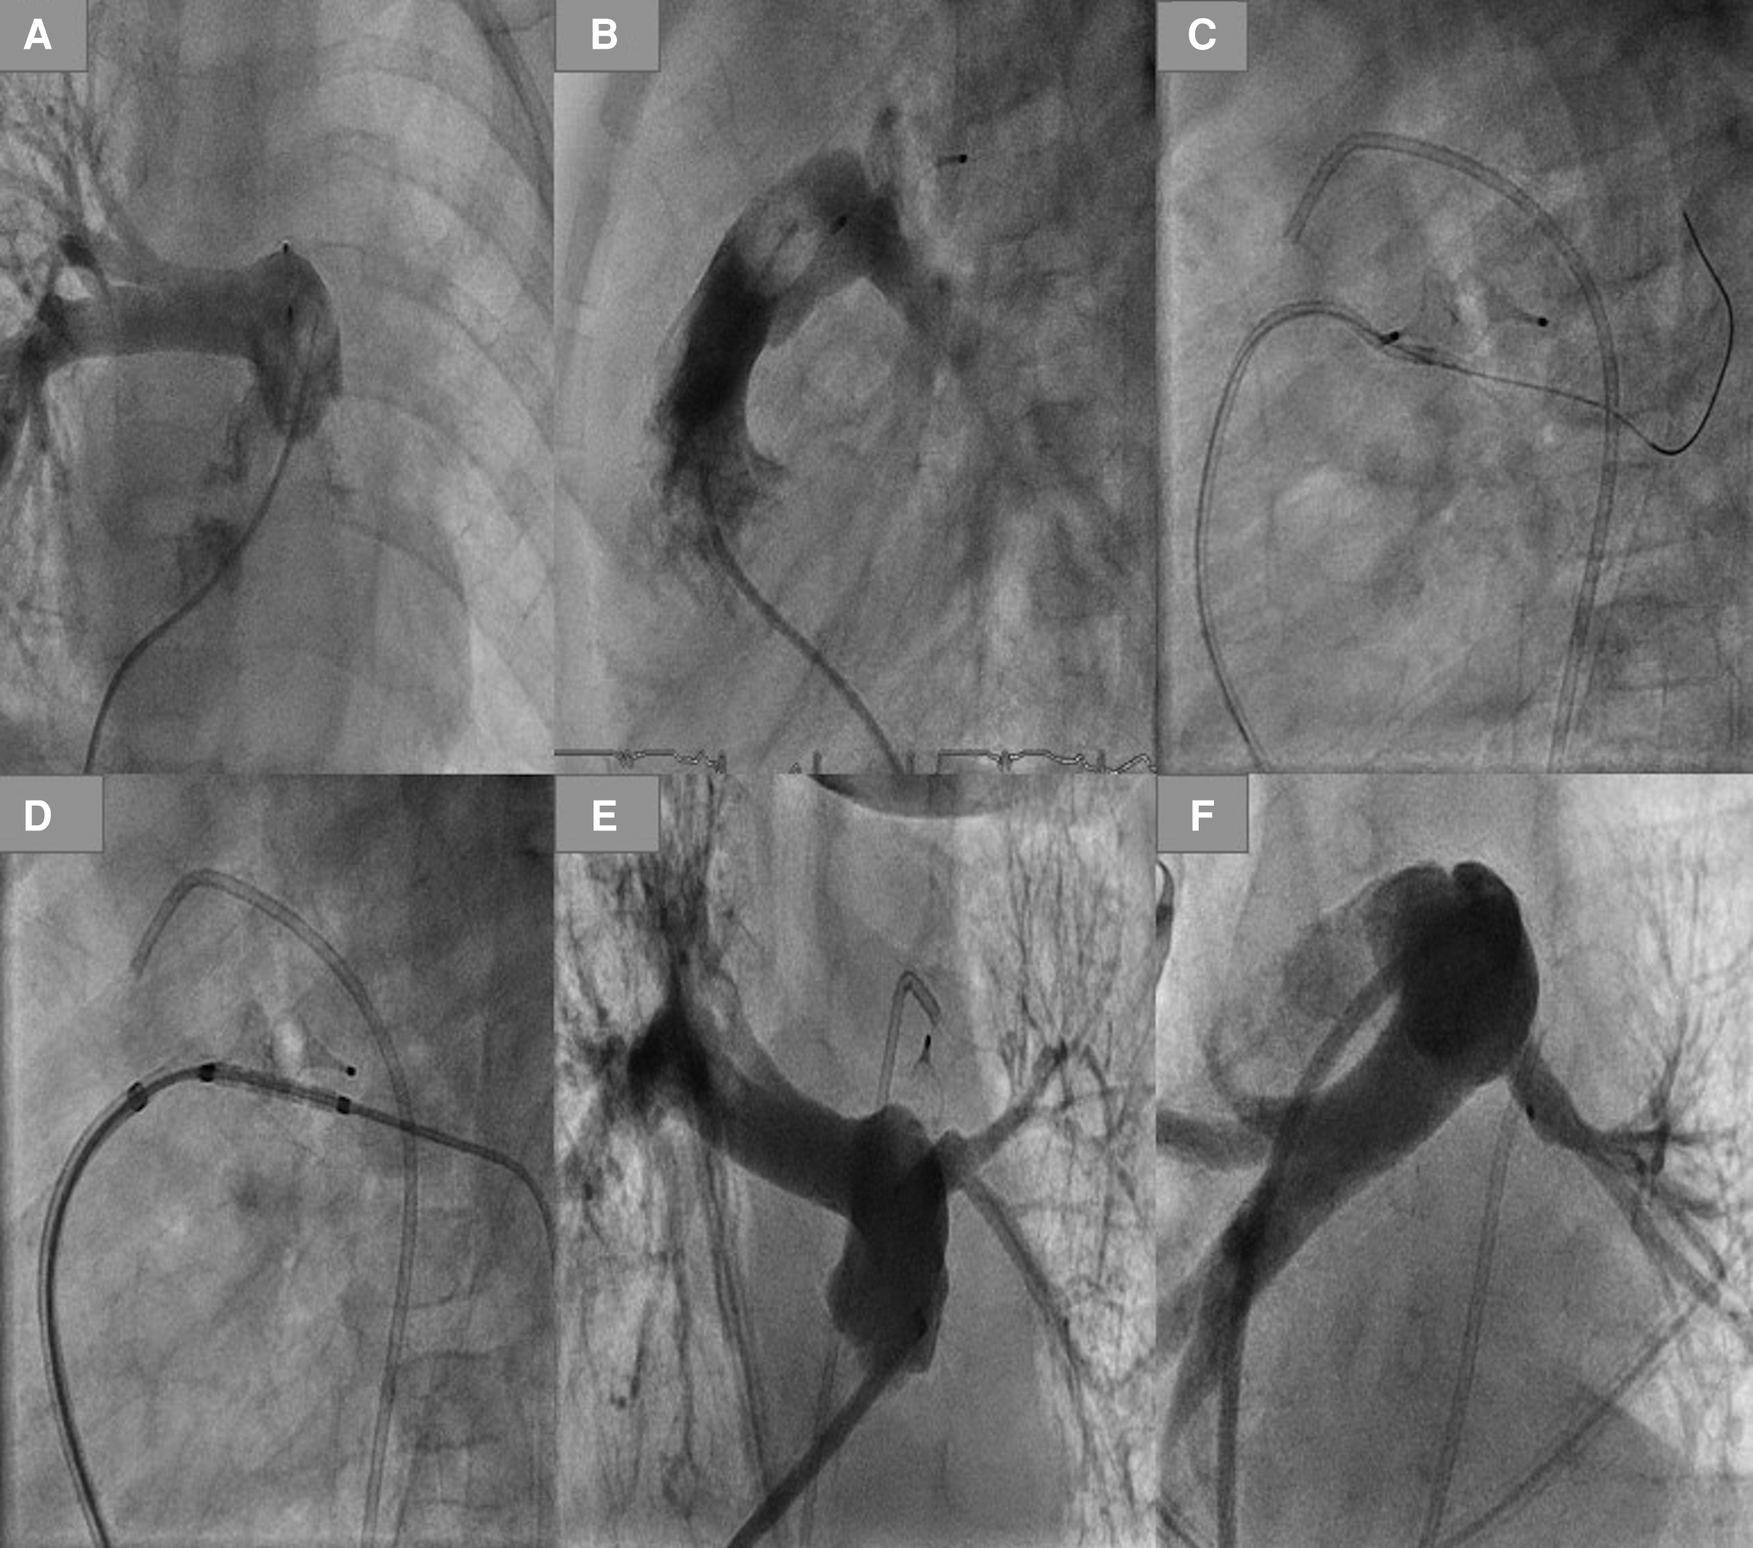

An AP4-related left pulmonary stenosis was documented in 2 patients born at 31 and 24 weeks' gestation and weighing at the intervention time 2,600 and 2,500 g, respectively. The first patient's duct was Type C and was occluded with an AP4 8 × 13.5 mm. The native LPA was hypoplastic (2 mm) and jailed by the AP4, causing LPA obstruction 3 months after the intervention. After discussing the surgical removal of the plug with PA plastic vs. reintervention by the surgeons, the decision for reintervention was made for the following reasons: first, the native LPA was hypoplastic (<2 mm), and the obstruction of the LPA was extended to the Helios; second, the patient had severe BPD and pulmonary hypertension (PH), which can increase the risk of the surgery. For these reasons, reintervention was in this patient superior to surgery. A rash reintervention was performed to recanalize the obstructed LPA; the balloon dilation of the recanalized LPA was ineffective, and a stent was required and implanted. Echocardiography in follow-up showed satisfactory development of the LPA (Figure 3). In the second patient, the LPA (3.5 mm) was jailed by the pulmonary side of the AP4 (7 × 12.5 mm), causing a narrowing of the LPA entrance (2 mm) without restriction of the LPA perfusion. We dilated the LPA 4 months after the closure of the duct. In follow-up, there was no need for a reintervention.

Figure 3

Plug-related left pulmonary obstruction with the required reintervention. (A,B) LPA obstruction in AP and lateral view. (C) Crossing the LPA using a coronary wire. (D) Balloon premounted stent positioned in LPA. (E,D) LPA after stenting.